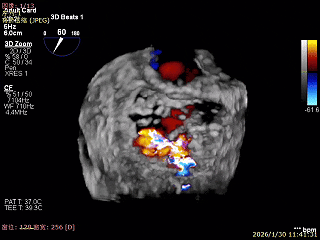

3D Enface 2区及3区前叶脱向左房

3D Enface 可见反流由2区3区从前后冲出

3D Enface下组织桥稳定残余外侧前叶脱垂

3D Enface上彩可见夹子内侧无反流,残余外侧反流

3D Enface下组织桥稳定无反流

夹子释放后,反流基本消失

LVOT切面可见主瓣二尖瓣术后反流基本消失